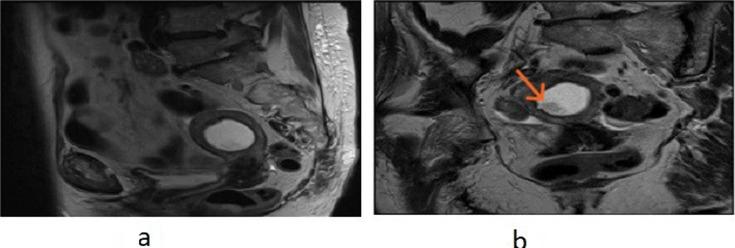

Histiocytic or xanthogranulomatous endometritis (XGE) is an extremely rare benign histopathological entity with only a few cases reported in literature to date. It is characterised by the replacement of endometrial tissue with sheets of foamy histiocytes, giant cells, lymphocytes and plasma cells; calcification and necrosis. It involves chronic inflammation and may be associated with endometrial hyperplasia, endometrial carcinoma and atrophy, causing cervical stenosis and recurrent pyometra, especially in postmenopausal women. We report a case of senile recurrent pyometra masquerading as pyelonephritis clinically and endometrial malignancy radiologically, confirmed later on histology as XGE. Due to deceptive manifestation and rarity of this clinical condition, it is very important for a gynaecologist, radiologist and histopathologist to have a clear understanding of this entity.

组织细胞性或黄色肉芽肿性子宫内膜炎(XGE)是一种极其罕见的良性组织病理学实体,迄今为止文献中仅报道了少数病例。其特征是子宫内膜组织被成片的泡沫状组织细胞、巨细胞、淋巴细胞和浆细胞取代;伴有钙化和坏死。它涉及慢性炎症,可能与子宫内膜增生、子宫内膜癌和萎缩相关,导致宫颈狭窄和复发性脓性子宫积脓,尤其是在绝经后女性中。我们报告一例老年复发性脓性子宫积脓病例,临床上伪装为肾盂肾炎,放射学上疑似子宫内膜恶性肿瘤,后来经组织学确诊为XGE。由于这种临床情况的表现具有欺骗性且罕见,妇科医生、放射科医生和组织病理学家清楚了解这一实体非常重要。